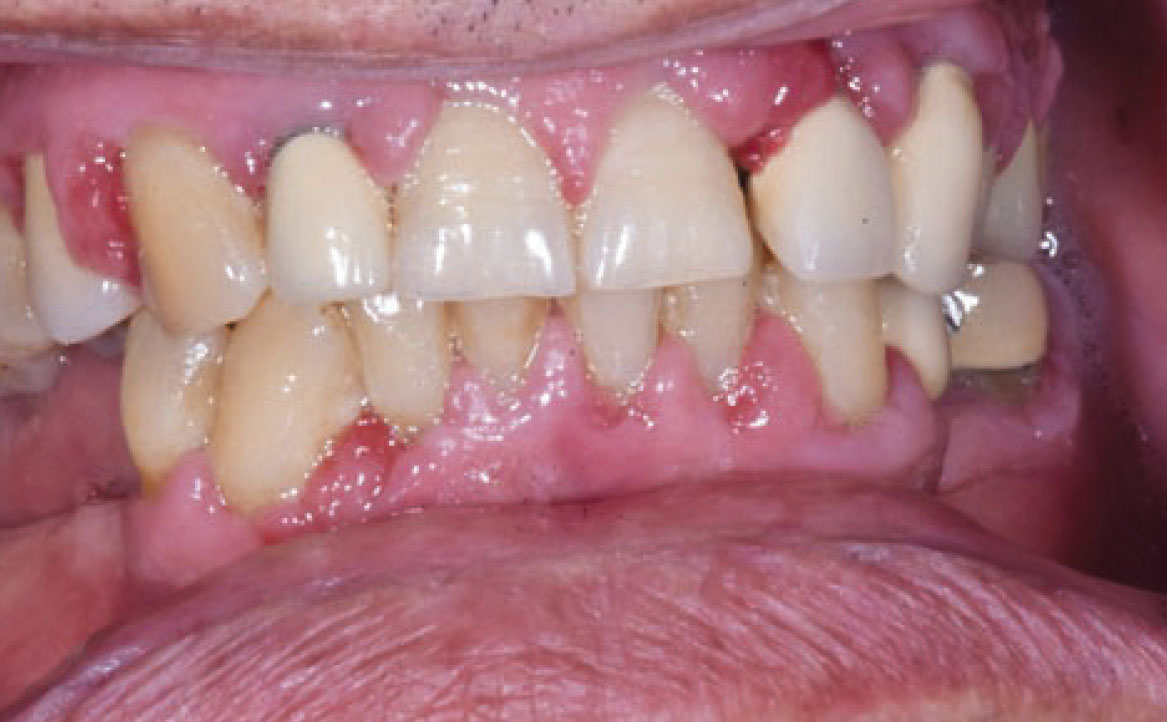

Le reazioni o lesioni lichenoidi orali presentano una similitudine clinica con le lesioni da lichen planus orale, sebbene si distinguano per una marcata componente eritematosa/erosiva e una distribuzione unilaterale delle lesioni, in particolare sulla mucosa geniena e sul dorso e margine laterale della lingua. Inoltre, a differenza del lichen planus, queste reazioni consentono di individuare la causa scatenante e vengono classificate in base all’agente causale coinvolto, che può essere il contatto diretto con materiali di restauro dentale o lesioni farmaco-correlate (17).

Più di 50 diversi farmaci sono stati associati a questo tipo di lesioni, tra cui i più comuni sono gli antipertensivi, compresi i β-bloccanti, gli ACE inibitori e i diuretici. In aggiunta, anche farmaci antidiabetici come le sulfaniluree (tolbutamide e glipizide), antimicotici come il ketoconazolo, anticonvulsivanti come la carbamazepina, farmaci immunomodulatori come i sali d’oro e la penicillamina, la sulfasalazina e l’allopurinolo sono stati segnalati come agenti responsabili delle LR (fig. 3) Questi farmaci sono spesso utilizzati in combinazione, suggerendo un possibile effetto sinergico (19).